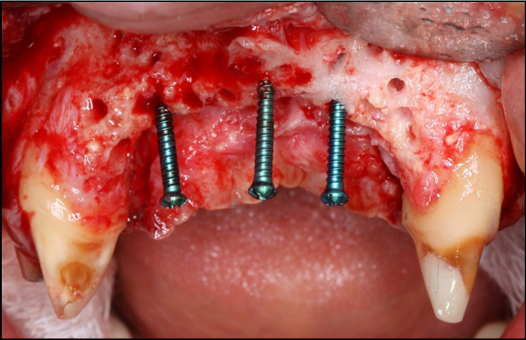

The surgical procedure was done under intravenous sedation using Fentanyl and Versed. Local anesthetic was used and a supra-crestal horizontal incision made on the palatal aspect of the anterior maxilla. A mucoperiosteal flaps were elevated, exposing a severely resorbed ridge of the pre-maxilla (Figure 2). Decortication was conducted with a round carbide bur in order to perforated the cortical aspect of the bone and expose the cancellous bone, to increase vascularity to the recipient site. Three screws were fixed parallel to the adjacent teeth, serving as “tent pole”. The screws had 14 mm length and approximately 6-8 mm of the tenting screws were exposed to the oral cavity (Figure 3). An absorbable collagen sponge (ACS) carrier/matrix was embedded with 12 mg of rhBMP-2 at 1.5 mg/mL (Infuse® Medtronic Sofamor Danek, Memphis, TN, USA) and allowed to absorb for approximately 20 min. The rhBMP-2/ACS was cut into strips, half of the strips were added to the natural bone mineral component derived from bovine bone (Geistlich Bio-Oss® granules small - 0.25 to 1 mm, Geistlich Pharma, Germany). Initially, some strips of rhBMP-2/ACS were placed over the buccal aspect of the residual alveolar ridge of the pre-maxilla, followed by strips mixed with bovine bone (Figure 4). The three screws were fully covered by rhBMP-2/ACS strips. Finally, a titanium mesh was adapted over the entire rhBMP-2/ACS graft and fixed with 2 monocortical screws, one on the buccal aspect and one on the palatal aspect of the ridge, respecting a 2 mm distance from the mesh to the adjacent teeth (Figure 5). Extensive undermining incision was conducted on the apical aspect of the buccal flap in order to achieve primary closure.

Figure 3.Frontal view of the pre-maxilla after elevation of amucoperiosteal flap. Note 6-8 mm of the tenting screws length are exposed.